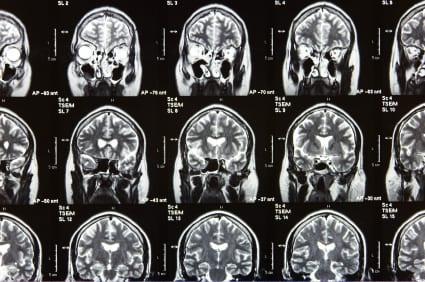

An aneurysm occurs when the wall of a blood vessel weakens and balloons outward, making the blood vessel abnormally large.

The larger the vessel becomes, the greater the risk of rupture – a serious emergency. Often there are no symptoms of an aneurysm until a rupture occurs. Brain (also known as intracranial) aneurysms are relatively common; up to 5% of people are thought to have one. Only a small fraction of these will ever rupture, however.